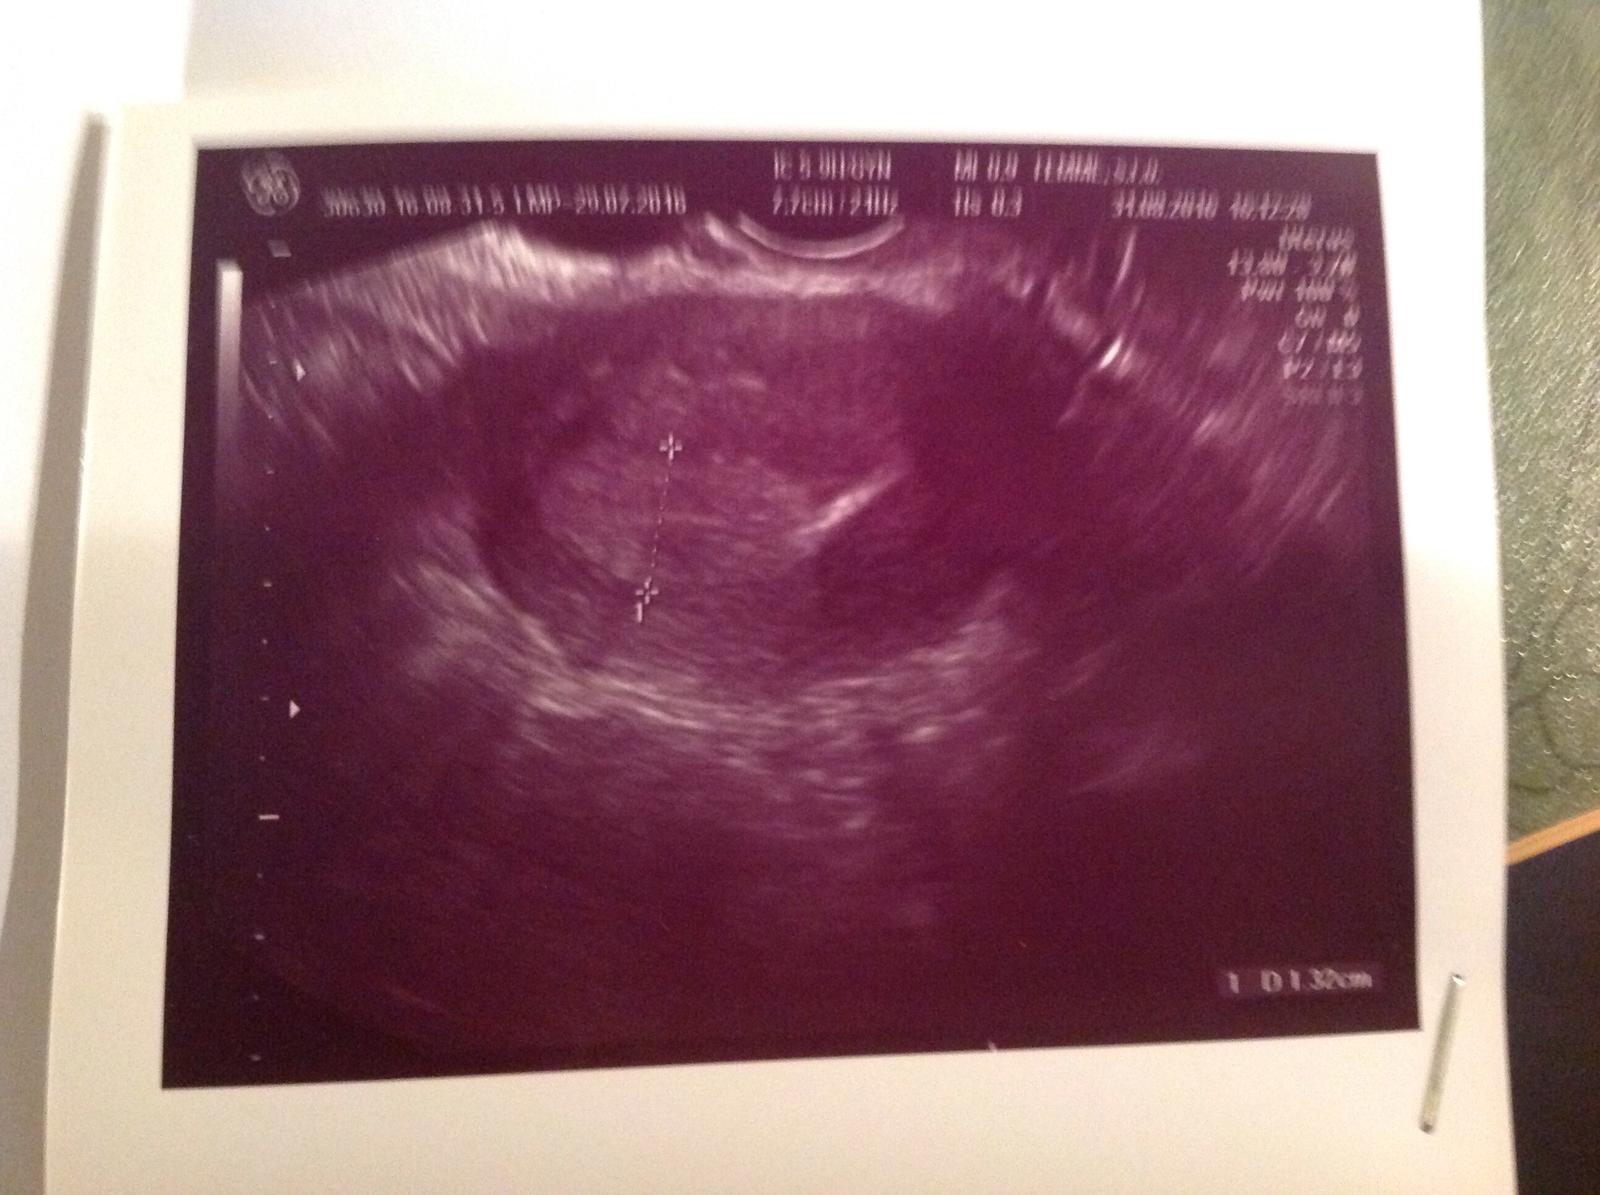

@nivea777 to co je na fotke. Nic ine neviem. Ale v pondelok idem k nej.